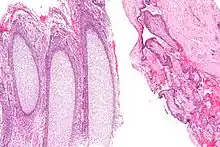

Products of conception, abbreviated POC, is a medical term used for the tissue derived from the union of an egg and a sperm. It encompasses anembryonic gestation (blighted ovum) which does not have a viable embryo.

In the context of tissue from a dilation and curettage, the presence of POC essentially excludes an ectopic pregnancy.

Recent studies indicate that the products of conception may be susceptible to pathogenic infections,[7] including viral infections. Indeed, footprints of JC polyomavirus and Merkel cell polyomavirus have been detected in chorionic villi from females affected by spontaneous abortion as well as pregnant women.[8][9] Another virus, BK polyomavirus has been detected in the same tissues, but with lesser extent.[8]